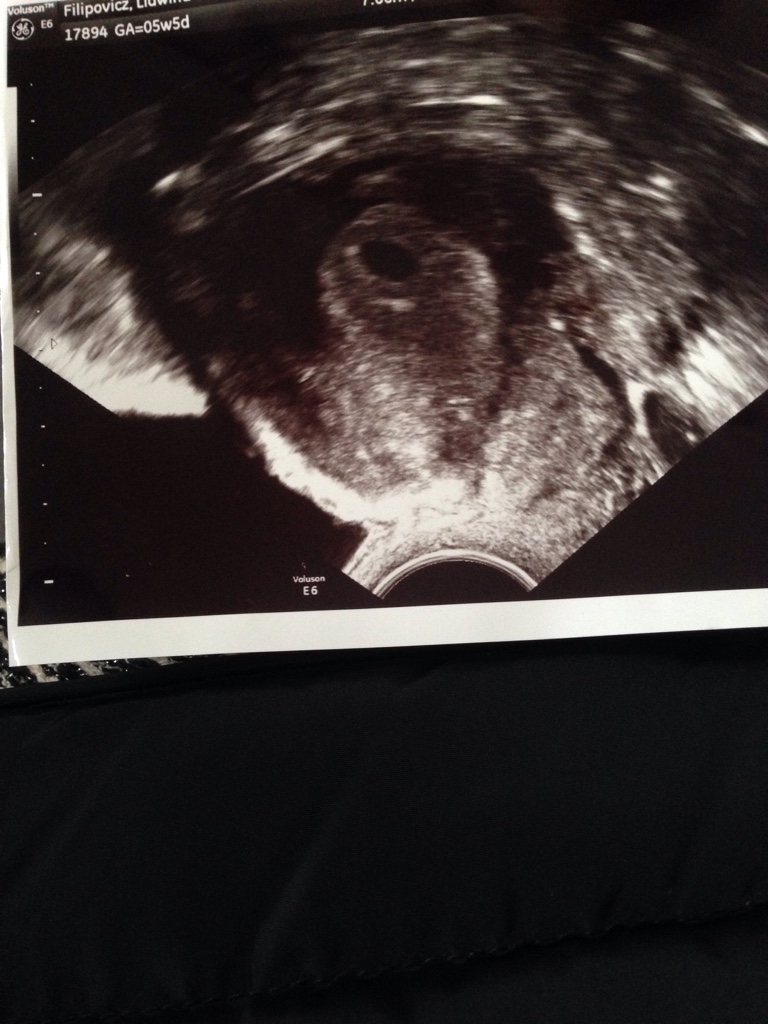

No wiec to 5 Tydz 5 dzuen nie ma jezxxe serduszka bo to 3 tyg Po zaplodnieniu

Nast Usg za dwa tyg to bedzie wiadomo czy zycie .... stresssssssss

1509630818-c9b14c582fcac5c4-aaaaaa.jpeg